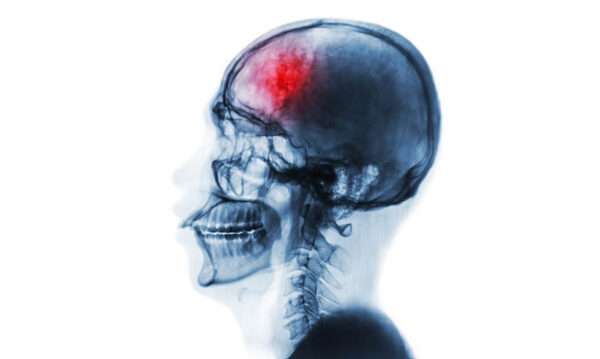

Las lesiones intracraneales, en su variedad de tipos, pueden ser una causa importante de cefalea debido a la alteración y desplazamiento de estructuras vasculares y otros tejidos sensibles al dolor dentro del cráneo. Este tipo de dolor de cabeza no es específico en cuanto a su localización, pero presenta patrones característicos que pueden ayudar en su identificación. En muchos casos, la cefalea asociada con una lesión intracraneal se agrava cuando la persona se recuesta, despertando al paciente durante la noche o alcanzando su intensidad máxima por la mañana, después de una posición recumbente prolongada durante la noche. Estos patrones son indicativos de la posible presencia de una masa intracraneal.

Un aspecto crucial que debe alertar a los médicos sobre la necesidad de realizar una imagenología cerebral es la aparición de un dolor de cabeza nuevo o que empeora en personas de mediana edad o mayores. A medida que la persona envejece, la posibilidad de que el dolor de cabeza esté relacionado con una lesión intracraneal aumenta, por lo que el reconocimiento temprano de estos signos es vital para el diagnóstico y tratamiento adecuados.

Además de estos síntomas sistémicos, los signos focales o difusos de disfunción cerebral, o los indicativos de un aumento de la presión intracraneal, como la presencia de papiledema (hinchazón del disco óptico debido a la presión intracraneal elevada), son indicadores cruciales que requieren investigación inmediata. El aumento de la presión dentro del cráneo es una situación grave que puede comprometer diversas funciones cerebrales y poner en riesgo la vida del paciente, lo que hace que la imagenología sea esencial para identificar la causa subyacente del dolor de cabeza y determinar el tratamiento adecuado.